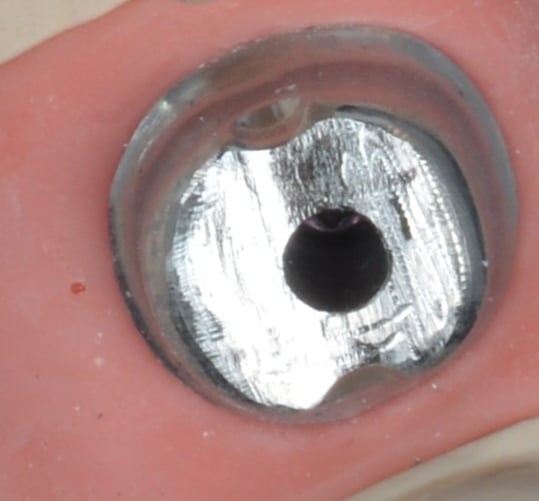

Die individuellen Abutments von Goodent werden auf Basis intraoraler Scans oder präziser Modelldaten konstruiert und exakt an die Anatomie, die Implantatangulation sowie den prothetischen Behandlungsplan des jeweiligen Patienten angepasst.

✔ Individualisiertes Emergenzprofil

✔ Korrektur der Implantatangulation

✔ Stabiles periimplantäres Weichgewebe

ei Goodent werden individuelle Abutments digital auf Basis intraoraler Scans und CBCT-Daten entworfen und aus Titan oder Zirkoniumdioxid präzise gefräst.

Sie sind mit allen gängigen Implantatplattformen kompatibel und als verschraubte oder zementierte Lösungen verfügbar.

Durch die exakte Anpassung an Weichgewebe und prothetischen Plan sorgen unsere Abutments für einen optimalen Kronensitz, verbesserte Ästhetik und gesundes periimplantäres Gewebe – für Vertrauen vom Scan bis zum Lächeln.